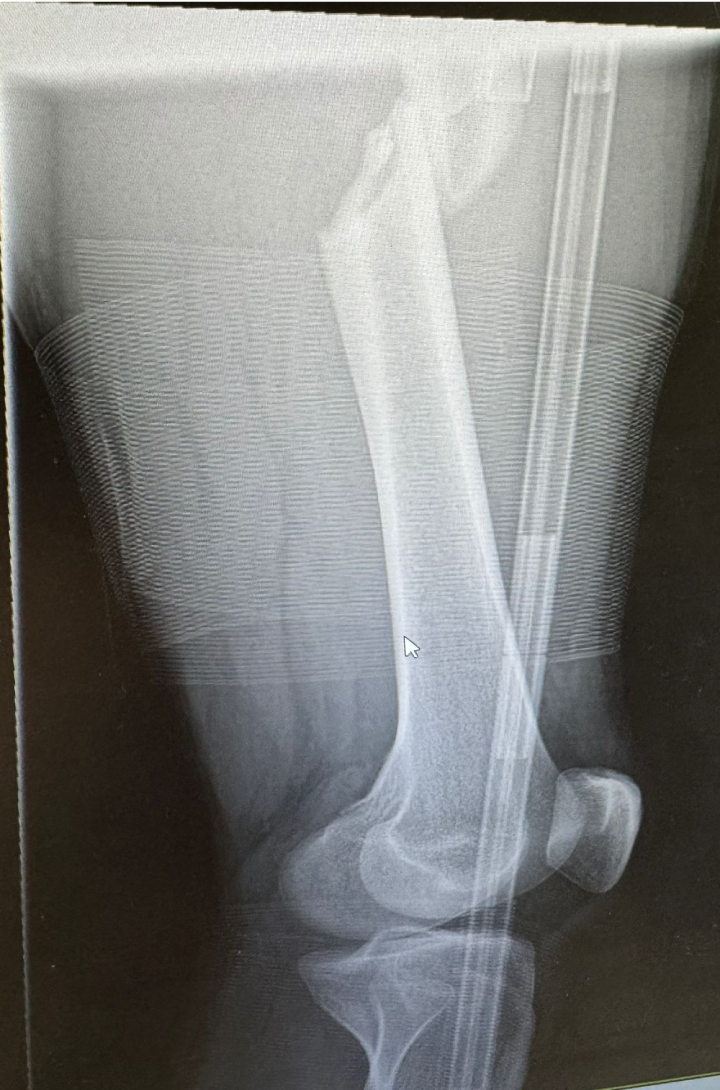

On 2nd November 2025, Cain was involved in a freak accident while playing football. After a long wait for emergency services, he was taken to hospital where it was confirmed he had suffered a serious femur break. Following surgery, Cain now faces months of rehabilitation and assisted walking, with hopes of returning to football in about a year.